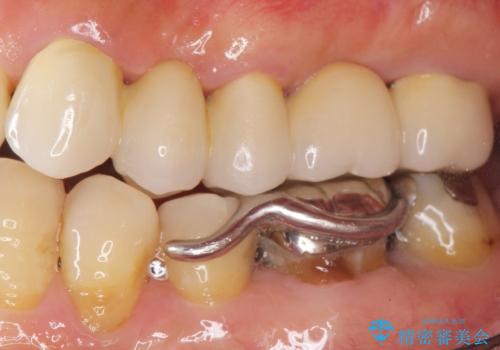

保存不可能な歯(左上4)を抜去後、ブリッジによる補綴治療を行いました。

自然な仕上がりと咬み心地に喜んで下さいました。

歯茎の腫れも治り、ご満足頂けました。

クラウンの種類:メタルボンドクラウン エコノミー